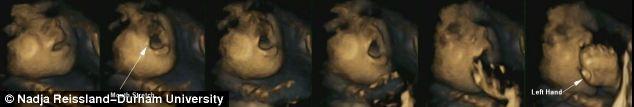

Dr. Reissland şi colegii ei de la Durham University au folosit aşa-numita ecografie 4-D – imagini ecografice 3-D care pot fi văzute în timp real – pentru a realiza imagini a 8 fetiţe şi 7 băieţi, în fiecare lună a sarcinii, între a 24-a şi a 36-a săptămână de sarcină.

În stadiile mai timpurii ale sarcinii, cercetătorii au putut observa cum bebeluşii îşi atingeau partea superioară şi părţile laterale ale capului, iar mai târziu treceau şi la atingerea părţilor inferioare, mai sensibile, ale feţei şi gurii.

Până în săptămâna a 36-a, majoritatea copiilor deschideau gura înainte de a şi-o atinge – un semn că anticipau atingerea. La copiii sănătoşi, sensibilitatea zonei din jurul gurii creştea pe măsură ce se dezvoltau, ceea ce ar putea însemna că ei deveneau mai conştienţi de mişcările gurii. Oamenii de ştiinţă cred că o anumită succesiune de mişcări, precum deschiderea gurii înainte de sugerea degetului, arată că la copil se dezvoltă deja intenţia, executarea unei mişcri cu un anumit scop.